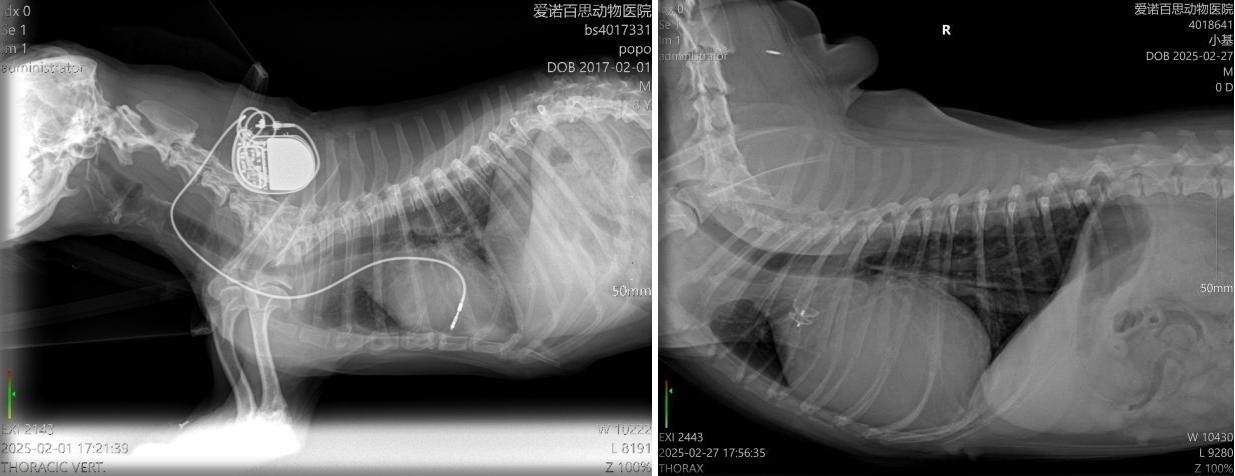

除了为多只病犬实施介入手术,让它们重获新生。更令人振奋的是,郭魏彬团队还成功为老年犬DUDU实施了心脏起搏器植入术,这也是广州首例以介入方式开展的犬心脏起搏器植入手术。

当时,DUDU因严重的心脏房室传导阻滞导致心动过缓,每分钟心率仅30次左右,经常出现突然晕厥的情况。“看着它一次次突然倒地,我们的心都碎了。”宠主说道。在得知可以通过介入方式给DUDU植入心脏起搏器后,宠主果断选择给DUDU进行手术。最终,DUDU的手术圆满完成。术后,DUDU的心率恢复到了正常水平,生活质量也得以显著改善。